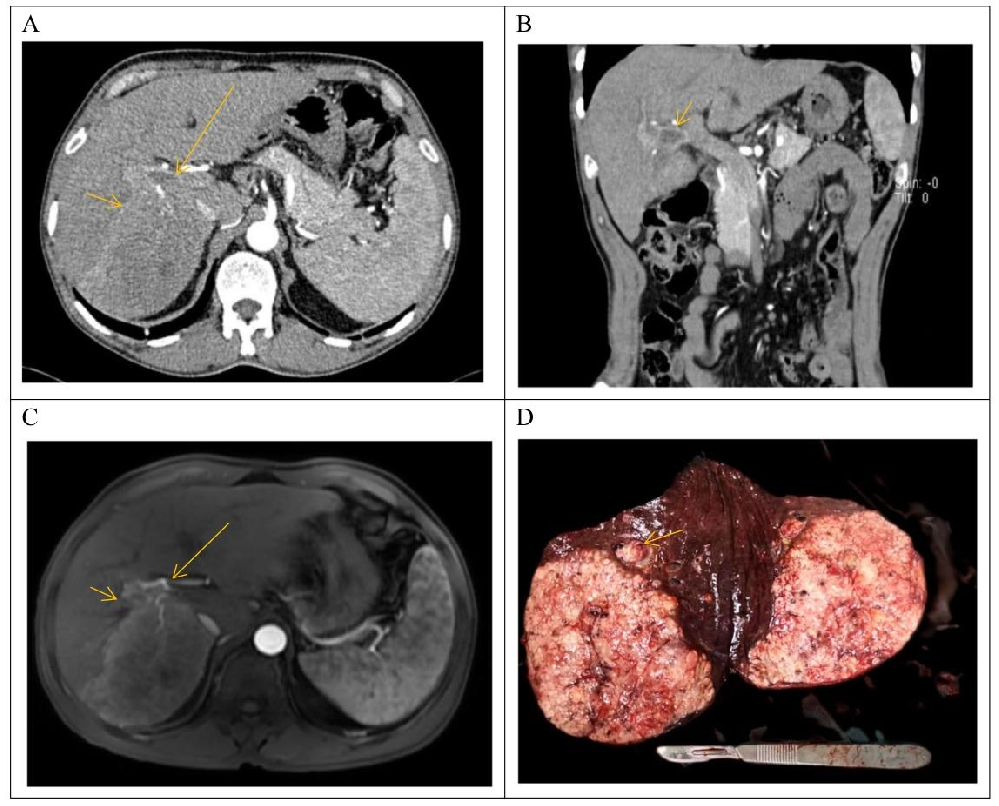

图1:患者临床资料

图1呈现细胞系来源的患者背景:① 术前CT/MRI显示肝右后叶病灶(动脉期强化)及门静脉右支癌栓(图1A-C);② 手术标本肉眼可见血管内癌栓(图1D);③ 患者病理特征:Edmondson-Steiner分级III-IV级,微血管侵犯(MVI)M2级,AFP>1000 IU/mL,CEA 4.0ng/mL,CA199 19.0U/mL(图1E),证实为晚期乙肝相关HCC。